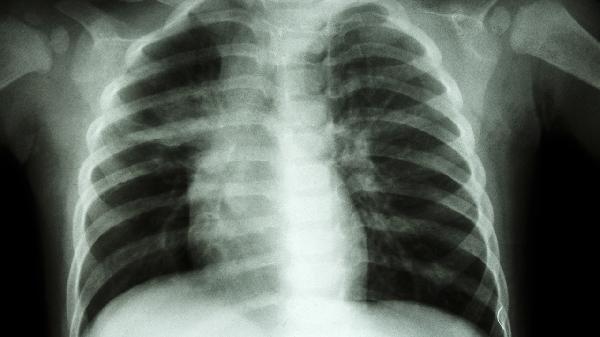

丹参酮与虎杖提取物可抑制成纤维细胞增殖,延缓矽结节形成。适用于接触矽尘10年以上的患者,能减轻CT显示的磨玻璃样改变。需持续用药3-6个月,期间定期复查高分辨率CT评估疗效。